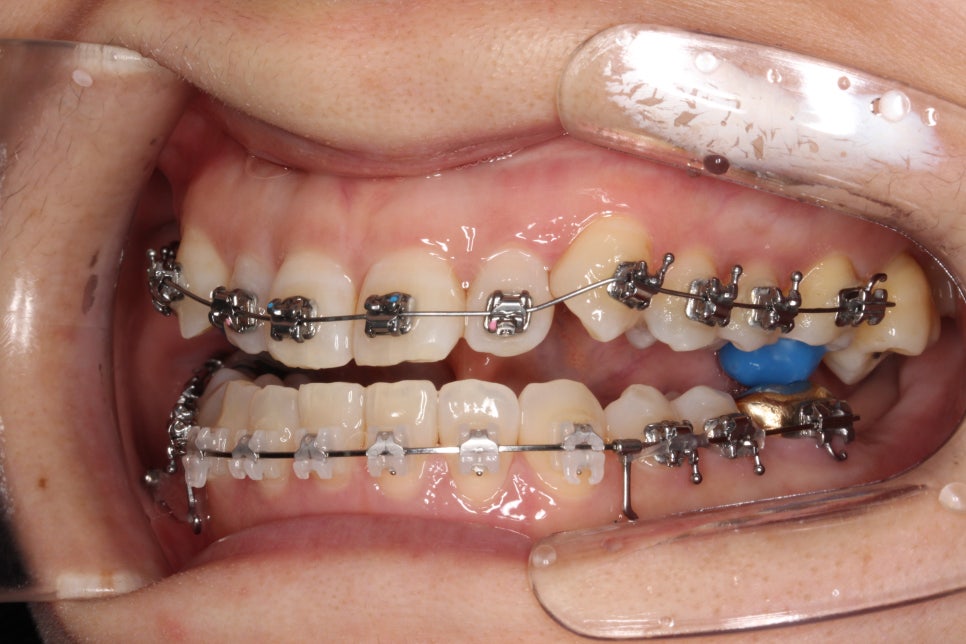

치료를 시작한지 얼마 되지 않았을 때의 모습입니다.

아래쪽은 미니스크류를 식립하여 당기고 있고, 앞니가 넘어올 수 있게 어금니에 #바이트블록 을 올렸습니다.

밥먹을 때 힘드셨을 겁니다 ㅠ